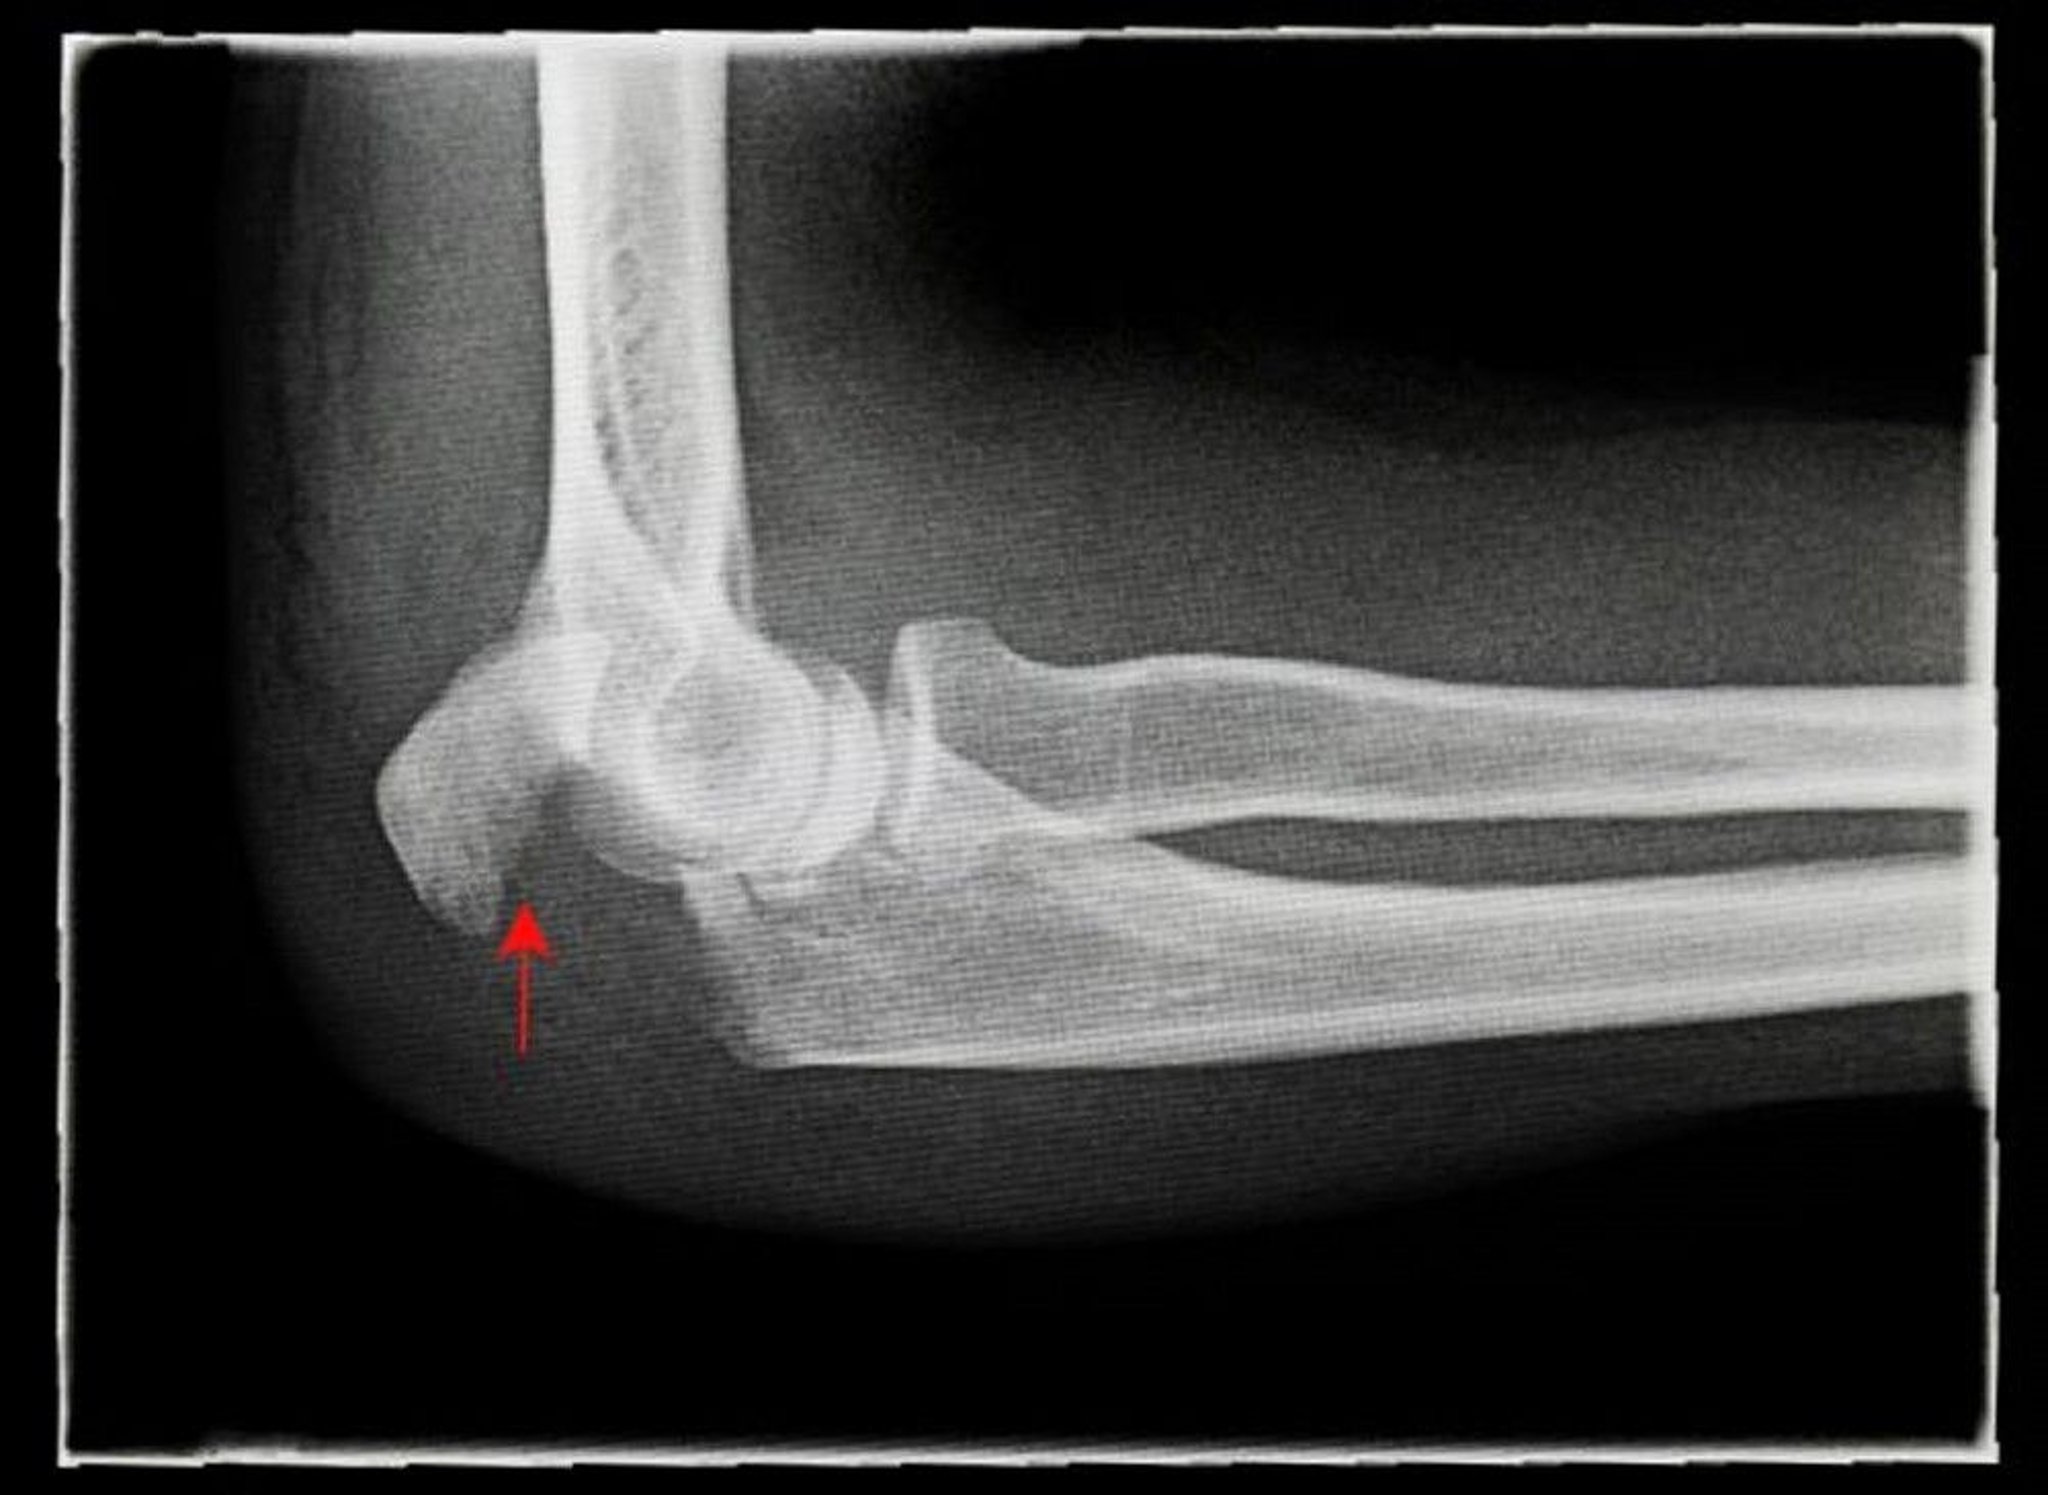

転位のある肘頭骨折

このX線写真には、転位のある肘頭骨折(矢印)の側面像が写っています。

ANTONIA REEVE/SCIENCE PHOTO LIBRARY